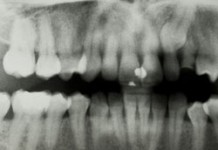

Рентгенография зубов

Рентгенография зубов – метод исследования, направленный на получение снимка зуба и полости рта. Рентгеновские лучи – вид электромагнитного излучения; такие лучи способны проникать сквозь...